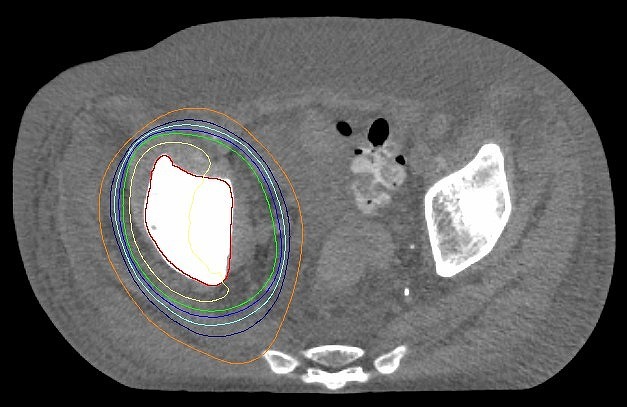

併存疾患のため手術できず薬物療法と放射線治療の併用療法で根治を目指した。

IMRTを用いて直腸がん自体には高線量を、転移しやすいリンパ節領域には予防的な線量を照射。